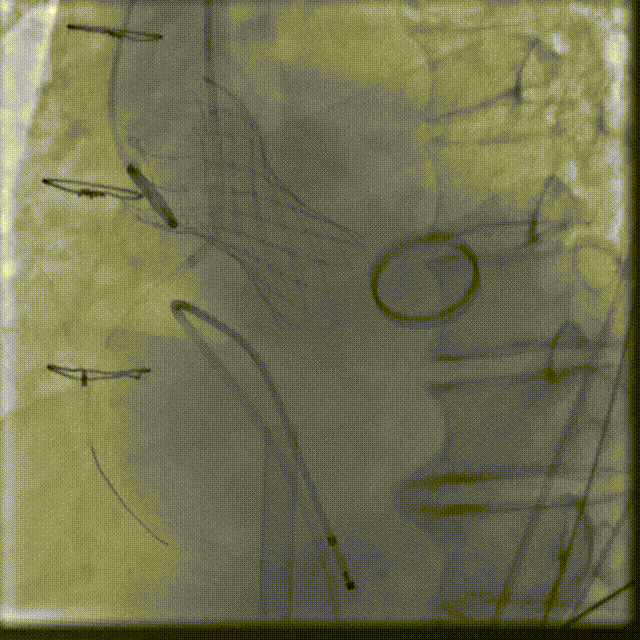

在右股动脉穿刺建立通路后,将右冠送入冠脉保护,后顺利送入大鞘,经食道超声及血管造影确认路径稳定,将ProStyle A ® AV32号瓣膜精准释放于目标位置(瓣下2mm),超声显示无瓣周漏,平均跨瓣压差4mmHg,心功能明显改善,患者生命体征平稳。

右冠保护 同时主动脉根部造影

定位